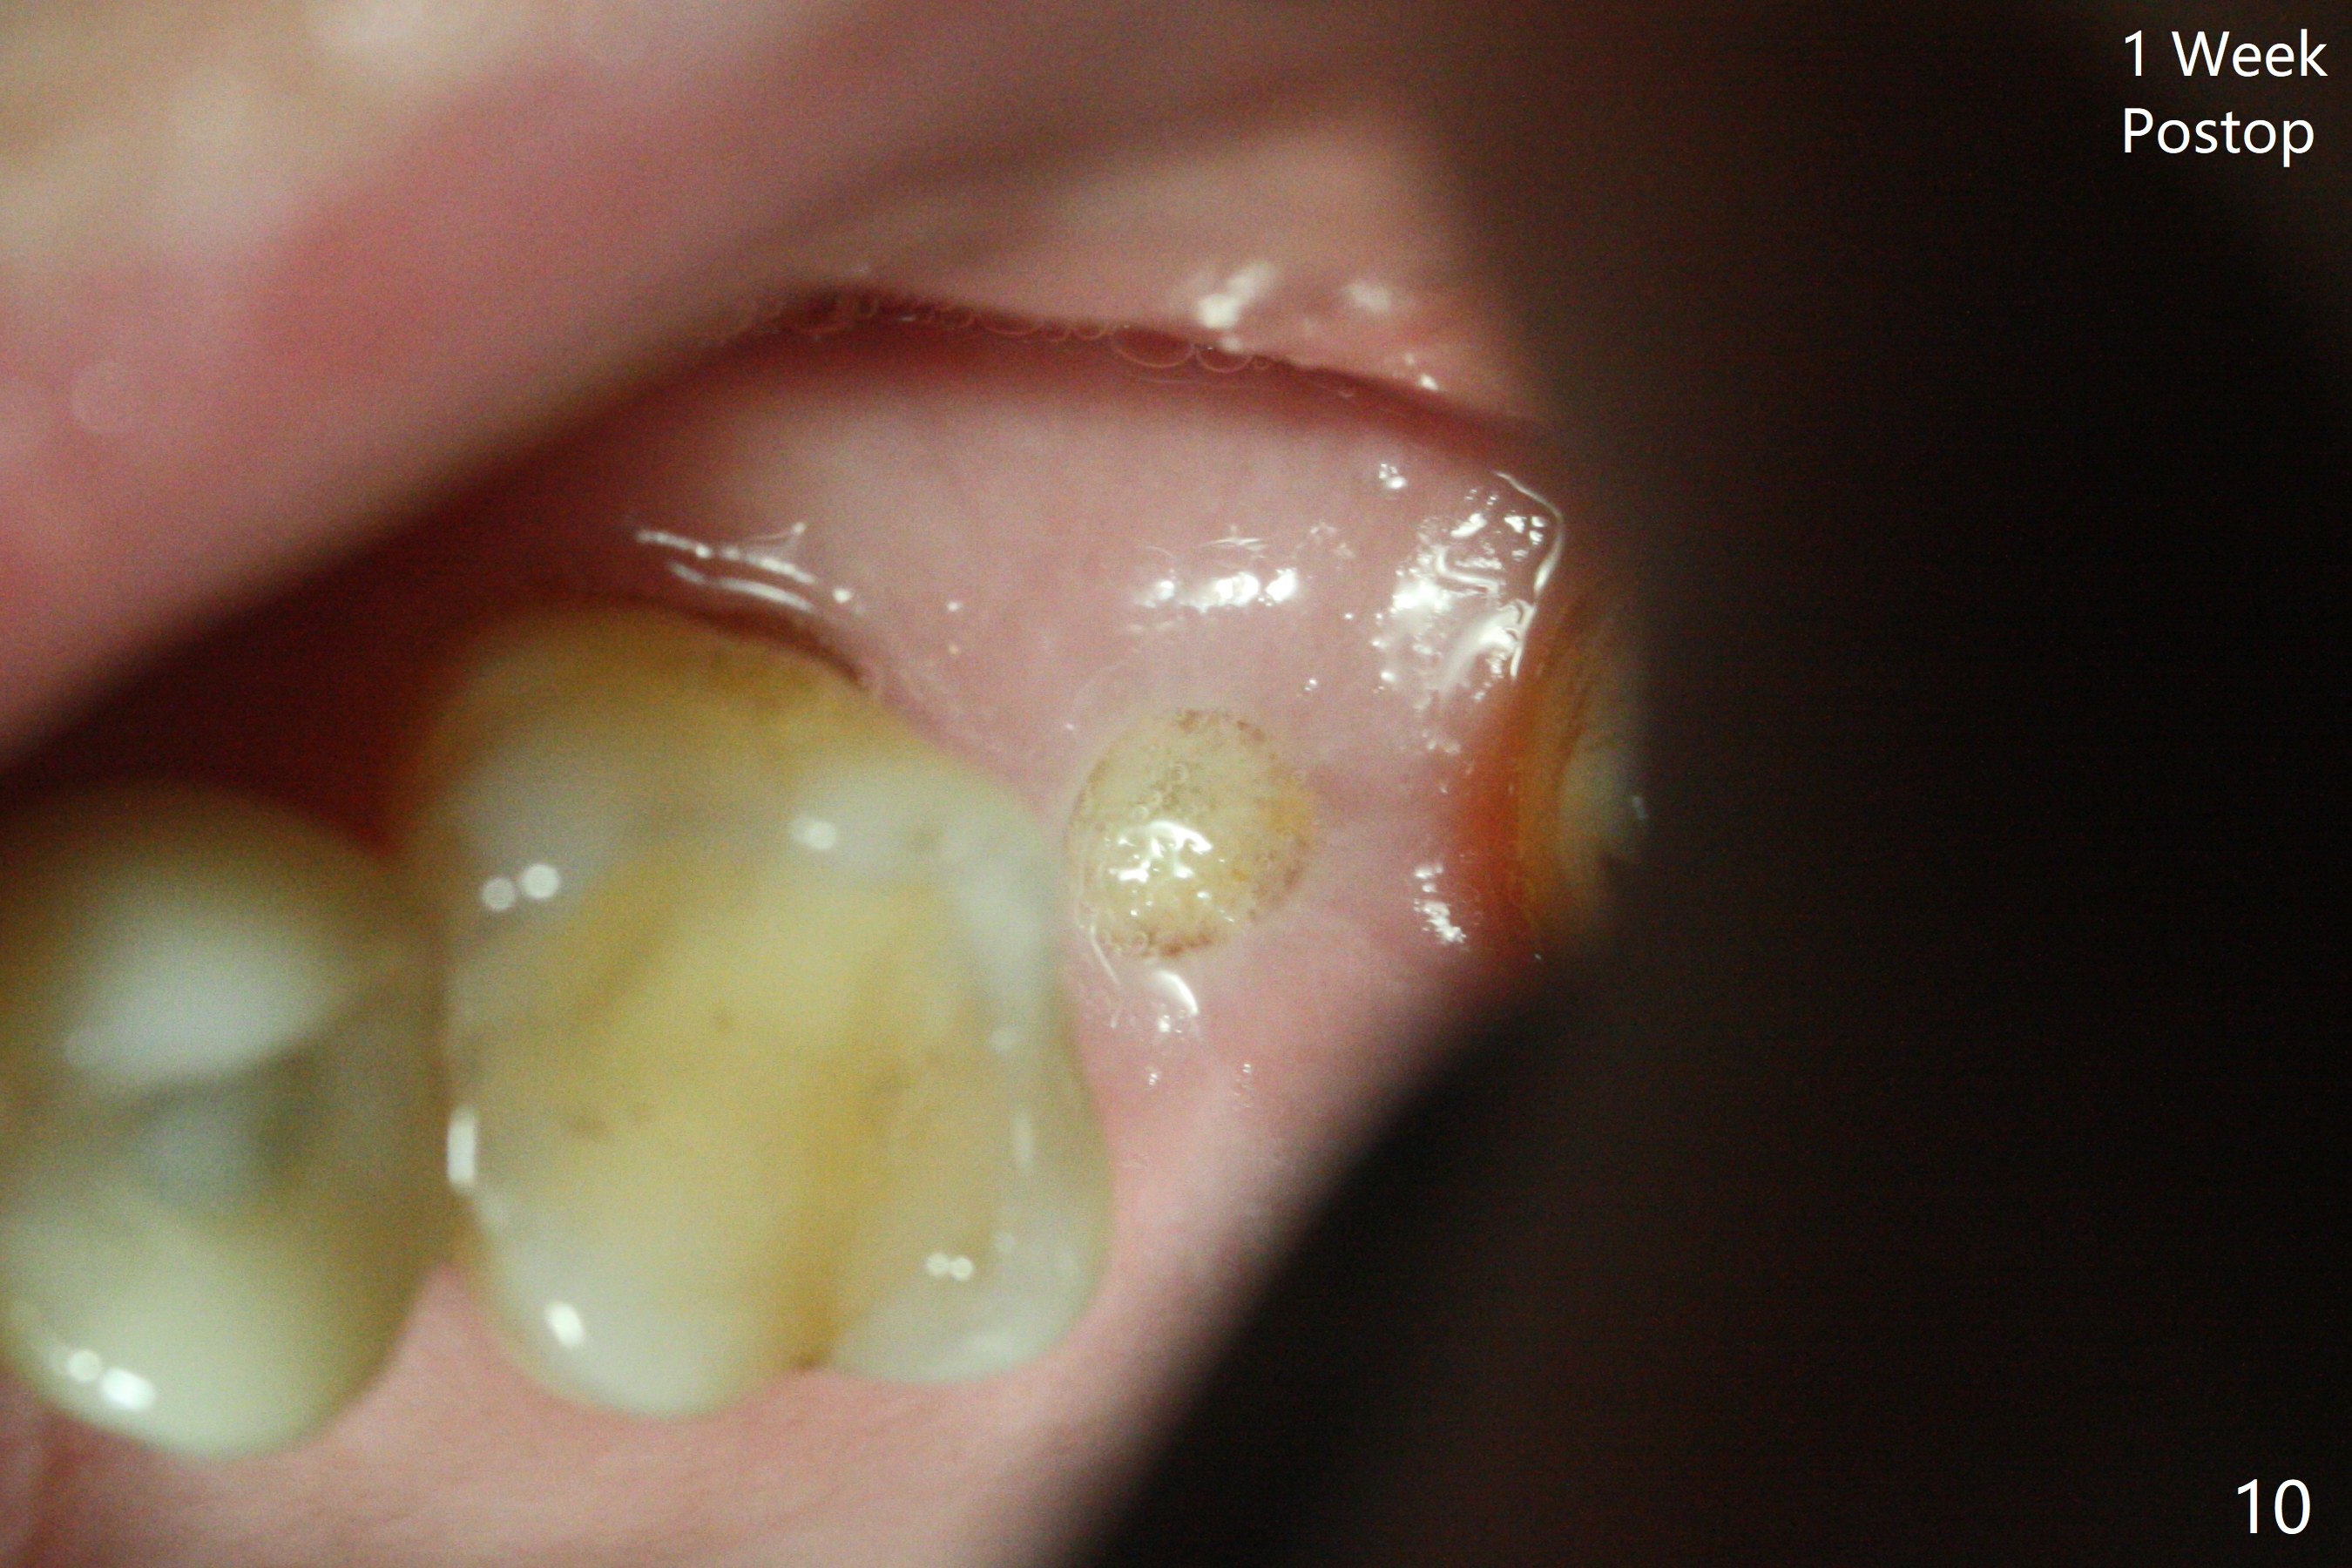

导板延期种植,如果角化龈充足,使用环形切刀,手术简化,达到无痛或者少痛目的。但是当扭力不够时,伤口关闭是个小难题。一种处理方法,放置胶原膜,利用牙周胶水固定,避免缝线,进一步简化手术步骤,助手可以完成。

66岁男右上,左上7导板延期种植(足够角化龈,使用环形切刀),都提升,但是前者未植骨(图一,二(骨高度多,进入上颌窦少)),后者植骨(图六(*),七),由于扭力低(小于15Ncm),放置愈合螺帽和剪成圆形六个月胶原膜,使用牙周胶水(图三,八),之后不再放置牙周敷料。当钻头接近左侧上颌窦底板时,放置骨粉(图四-六:*),使用报废植体(图四,五)和正式植体(图六)将骨粉推入上颌窦。术后病人抱怨食物撞击伤口疼痛,即刻修复减少术后疼痛。术后5个月没有骨质吸收,基台完全就位(图十一,二)。